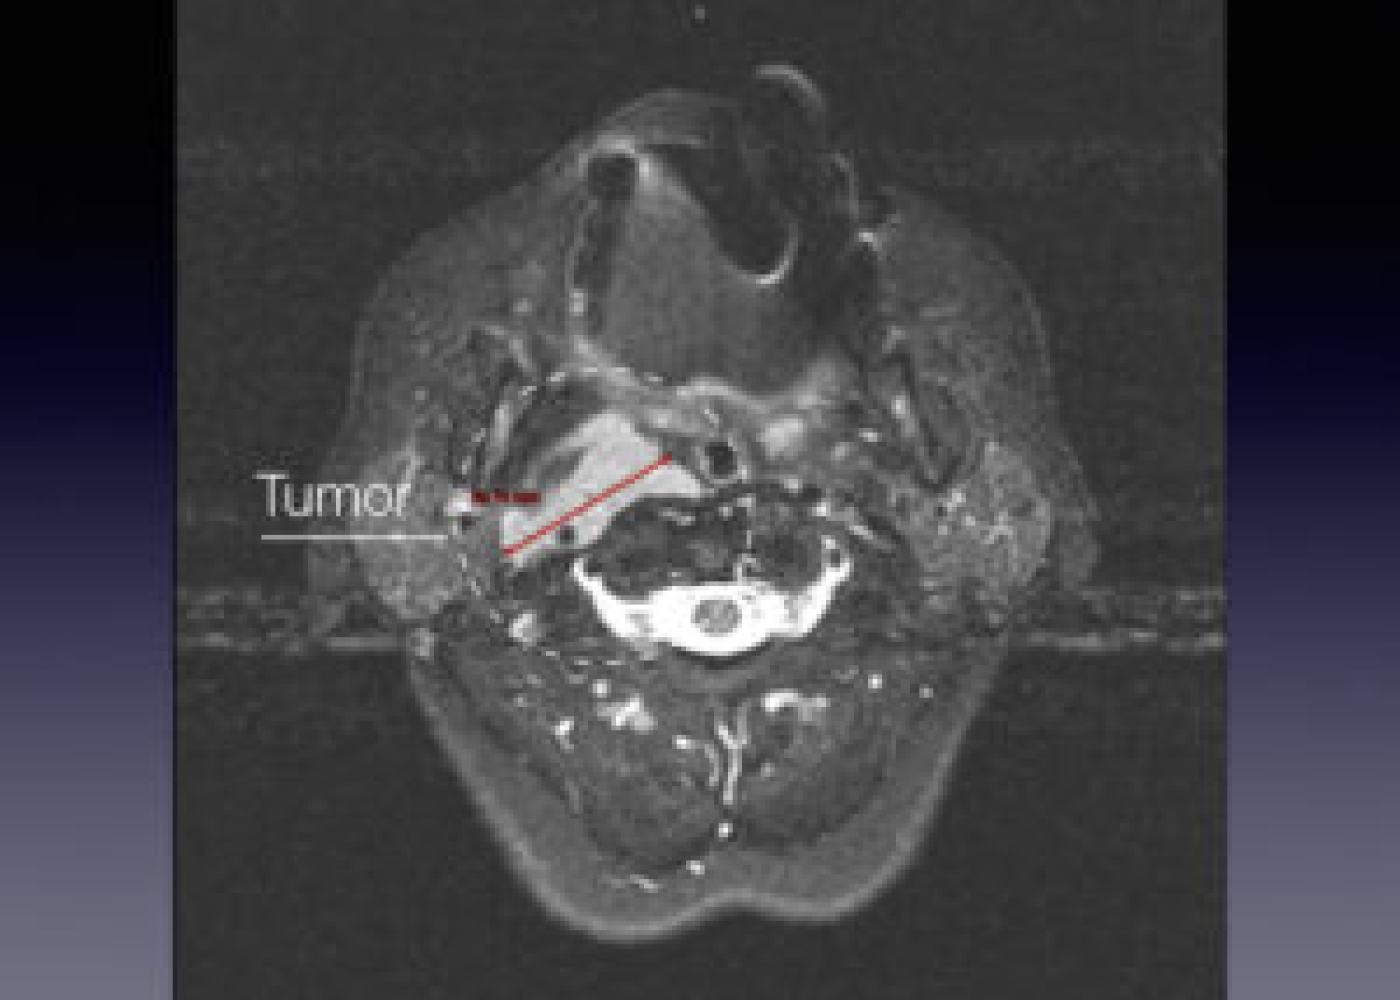

Պացիենտի խոսքով՝ գանգատներն ի հայտ են եկել մոտ 1,5 տարի առաջ և հաջորդիվ գոյացության չափերը զգալի մեծացել են: Հետազոտման ժամանակ աջից պարանոցի քնային եռանկյունում հայտնաբերվել է հստակ սահմաններով մոտ 4սմ տրամագծով անցավ գոյացություն:

Կլինիկոպարակլինիկական հետազոտությունների արդյունքում ախտորոշվել է քնային զարկերակի բիֆուրկացիայի անգիոմիոմատոզ համարտոմա աջից, որը ճնշում էր արտաքին քնային զարկերակը: